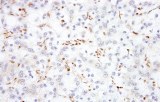

Primary antibodies for immunohistochemistry CE/IVD - Pediatric pathology

Perinatal/paediatric pathology is a medical subspecialty with particular expertise in diseases affecting the placenta, fetus, infant and child. Although many conditions that affect adults also affect children, pediatric pathology includes many conditions found only in patients younger than 18 years of age. One group of conditions involving the infant population is congenital anomalies. A malformation is a congenital anomaly due to an intrinsic defect in development. A disruption occurs when a normally developing organ is secondarily damaged by another process. A sequence is a collection of several anomalies, all of which are due to one malformation, disruption, or deformation. Finally, a syndrome is a group of related anomalies. An other group is the pediatric cancers or childhood cancers. Childhood cancers include many that also occur in adults. Leukemia is by far the most common, representing about 33% of childhood cancers, brain tumors represent about 25%, lymphomas represent about 8%, and certain bone cancers (osteosarcoma and Ewing sarcoma) represent about 4%.